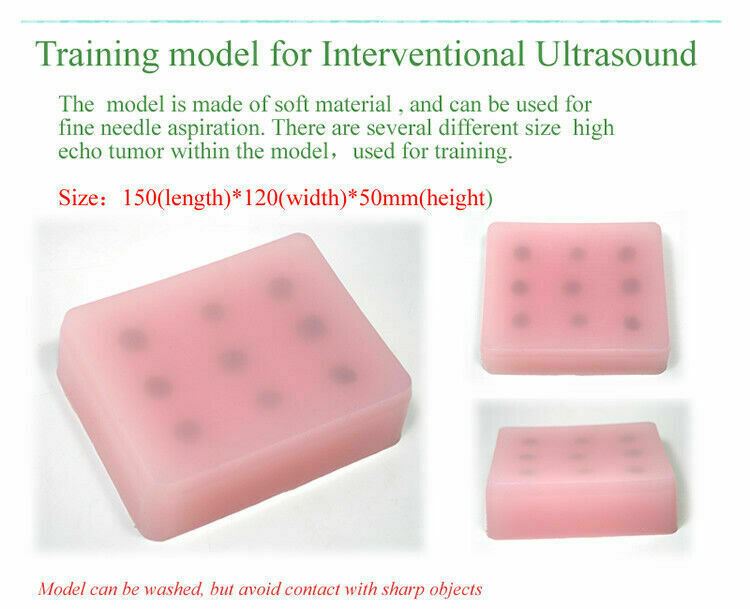

- A training teaching model for interventional Ultrasound

- Soft material

- Can be used for fine needle aspiration training

- Several different sized simulated high echo towers with the model

- 150x120x50mm

- Washable